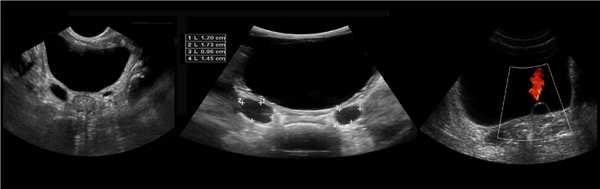

Клинический пример из первой группы. Пациент М., с хронической почечной недостаточностью. Трансплантация почки произведена от живого родственного донора. Трансплантат находится в правой подвздошной области. При нормальном функциональном состоянии трансплантата, показатели цветовой и спектральной допплерографии оценивались как удовлетворительные, с индексом резистентности не более 0,60 (рис. 1); показатели жесткости паренхимы почечного трансплантата при УЭСВ на различных участках составили от 20,05 до 29,18 кПа (рис. 2-4).

Рисунок 1. Ультразвуковое исследование в режиме цветовой и спектральной допплерографии в междольковых и сегментарных артериях у пациента М. Показатели кровотока в данном случае не изменены

Клинический пример из второй группы. Пациент К. перенес операцию пересадки почки от живого родственного донора. Трансплантат в левой подвздошной области. Индекс резистентности в междольковых артериях составил 0,70 (рис. 5). В сегментарных артериях индекс резистентности составил 0,66 (рис. 6). Показатели жесткости паренхимы почечного трансплантата при режиме УЭСВ составили от 31,6 до 36,9 кПа (рис. 7-9).

Рисунок 5. Исследование у пациента К. в режиме цветовой и спектральной допплерографии. Индекс резистентности в междольковых артериях почечного трансплантата составил 0,70

Рисунок 6. Эхограмма пациента К. Кровоток в сегментарных артериях неизменен